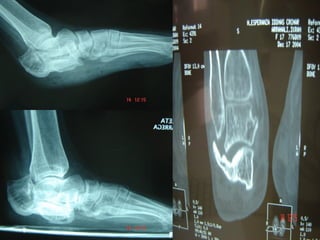

1-Postraumático

 Fracturas de astrágalo

Pie plano adquirido: fractura de

calcáneo

Ángulo de Böhler

Angulo de Gissane

Tratamiento: Fractura calcáneo

Fractura calcáneo

Fractura de escafoides

• #13 2ª fractura más frecuente del pie 60-70% superf cubierta de cartílago articular: vasc precaria. Explica necrosis astrágalo tras fractura de su cuello Fracturas de cuello astragalino (50%)por hiperdorsiflexión del pie en accidentes de trafico o caídas desde altura El astrágalo se empotra contra escafoides tarsiano, lo hunde: pie plano Dolor intenso en pie y tobillo con edema

• #14 El más frec fracturado, accidentes tráfico y caídas altura Hundimiento del astrágalo sobre la cara dorsal del calcáneo empotrándose en él. Sino IQ pie plano 3 tipos: Extraarticulares: buen pronóstico Intraarticulares: (75%) Mal pronóstico, se suele asociar con hundimiento. Perdida de longitud de la pierna: dismetrias

• #15 Se mide con una proyección lateral de Rx. En casos de fracturas, el ángulo está disminuido El ángulo de Böhler queda determinado por la intersección entre una línea que va desde la tuberosidad posterior del calcáneo hasta la faceta articular calcáneo-astragalina posterior, y otra desde el extremo calcáneo anterosuperior hasta este mismo punto. Angulo de Böhler (25-40º): su aplanamiento sirve para determinar la pérdida de masa ósea en las fracturas de calcáneo.

• #16 El ángulo crítico de Gissane es el que podemos medir en la intersección extiende desde la parte anterior del hueso hasta el borde posterior de la faceta subastragalina posterior. o. Su valor normal es de 100-110º y su disminución refleja la presencia de una fractura por compresión Este ángulo está en relación con la morfología del calcáneo que depende de su distribución trabecular y que conforma una gruesa columna cortical que se extiende desde la parte anterior del hueso hasta el borde posterior de la faceta subastragalina posterior. Se denomina ángulo crucial, descrito por Gissane en 1947 y su valor normal exhibe un amplio rango de entre 120 y 145° con promedio de 130°. Es de sumo valor en la evaluación de las lesiones traumáticas del calcáneo con involucro articular

• #18 No desplazadas: Inmovilización yeso 8 semanas Desplazadas Fracturas simples: Tornillos a compresión inter-fragmentos Fracturas completas: Placas atornilladas

• #22 Fractura luxación del escafoides tarsiano, el astrágalo se coloca entre los dos fragmentos de escafoides provocando un acortamiento del arco interno y un pie plano. Si existe desplazamiento de mas de 2mm hacer reducción y osteosintesis. Resto tto conservador yeso de 6-8 s. Fracturas de estrés típicas en atletas. Tto conservador Hacer diagnostico diferencial hueso accesorio navicular (10%)